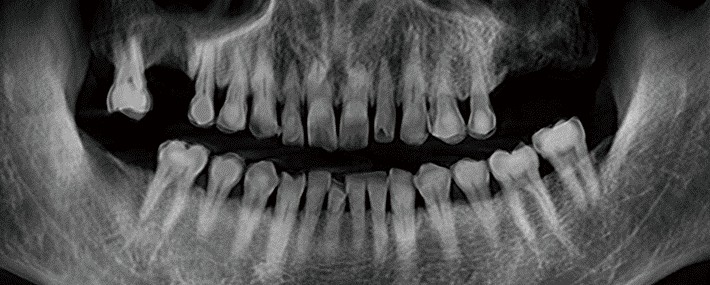

Panorama cu autofocalizare și algoritm de reducere a zgomotului de imagine

Datorită tehnologiei multi-strat, Rainbow™ CT captează și segmentează automat cele mai bune imagini, pe care le compilează într-o singură panoramă optimizată. Algoritmul de reducere a zgomotului (De-Noising) asigură calitatea superioară a imaginii, eliminând interferențele și detaliile nedorite.

Panoramă cu autofocalizare

Algoritm de reducere al interferentelor (DE-NOISING)